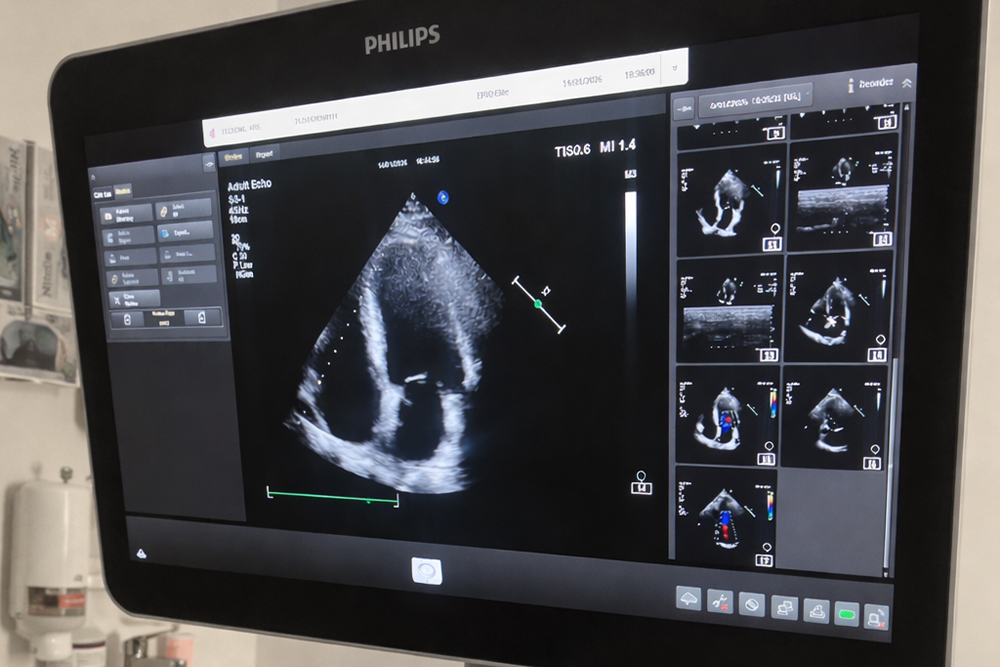

Neiromed klīnikā sirds ultrasonogrāfija (ehokardiogrāfija jeb EHO) ir drošs un nesāpīgs izmeklējums, kas ļauj ārstam detalizēti apskatīt sirdi un tās darbību. Izmeklējums tiek veikts ar mūsdienīgu, augstas precizitātes ultraskaņas iekārtu, kas nodrošina ļoti skaidru sirds attēlu un palīdz savlaicīgi pamanīt iespējamās veselības problēmas.

Uz krūškurvja tiek uzklāta speciāla želeja, kas palīdz iegūt kvalitatīvu attēlu. Ārsts ar ultraskaņas zondi pārbauda sirdi no dažādiem leņķiem. Izmeklējuma laikā var novērtēt sirds darbību, asins plūsmu un sirds vārstuļu stāvokli. Paralēli tiek uzraudzīta arī sirds darbība ar EKG monitoru.